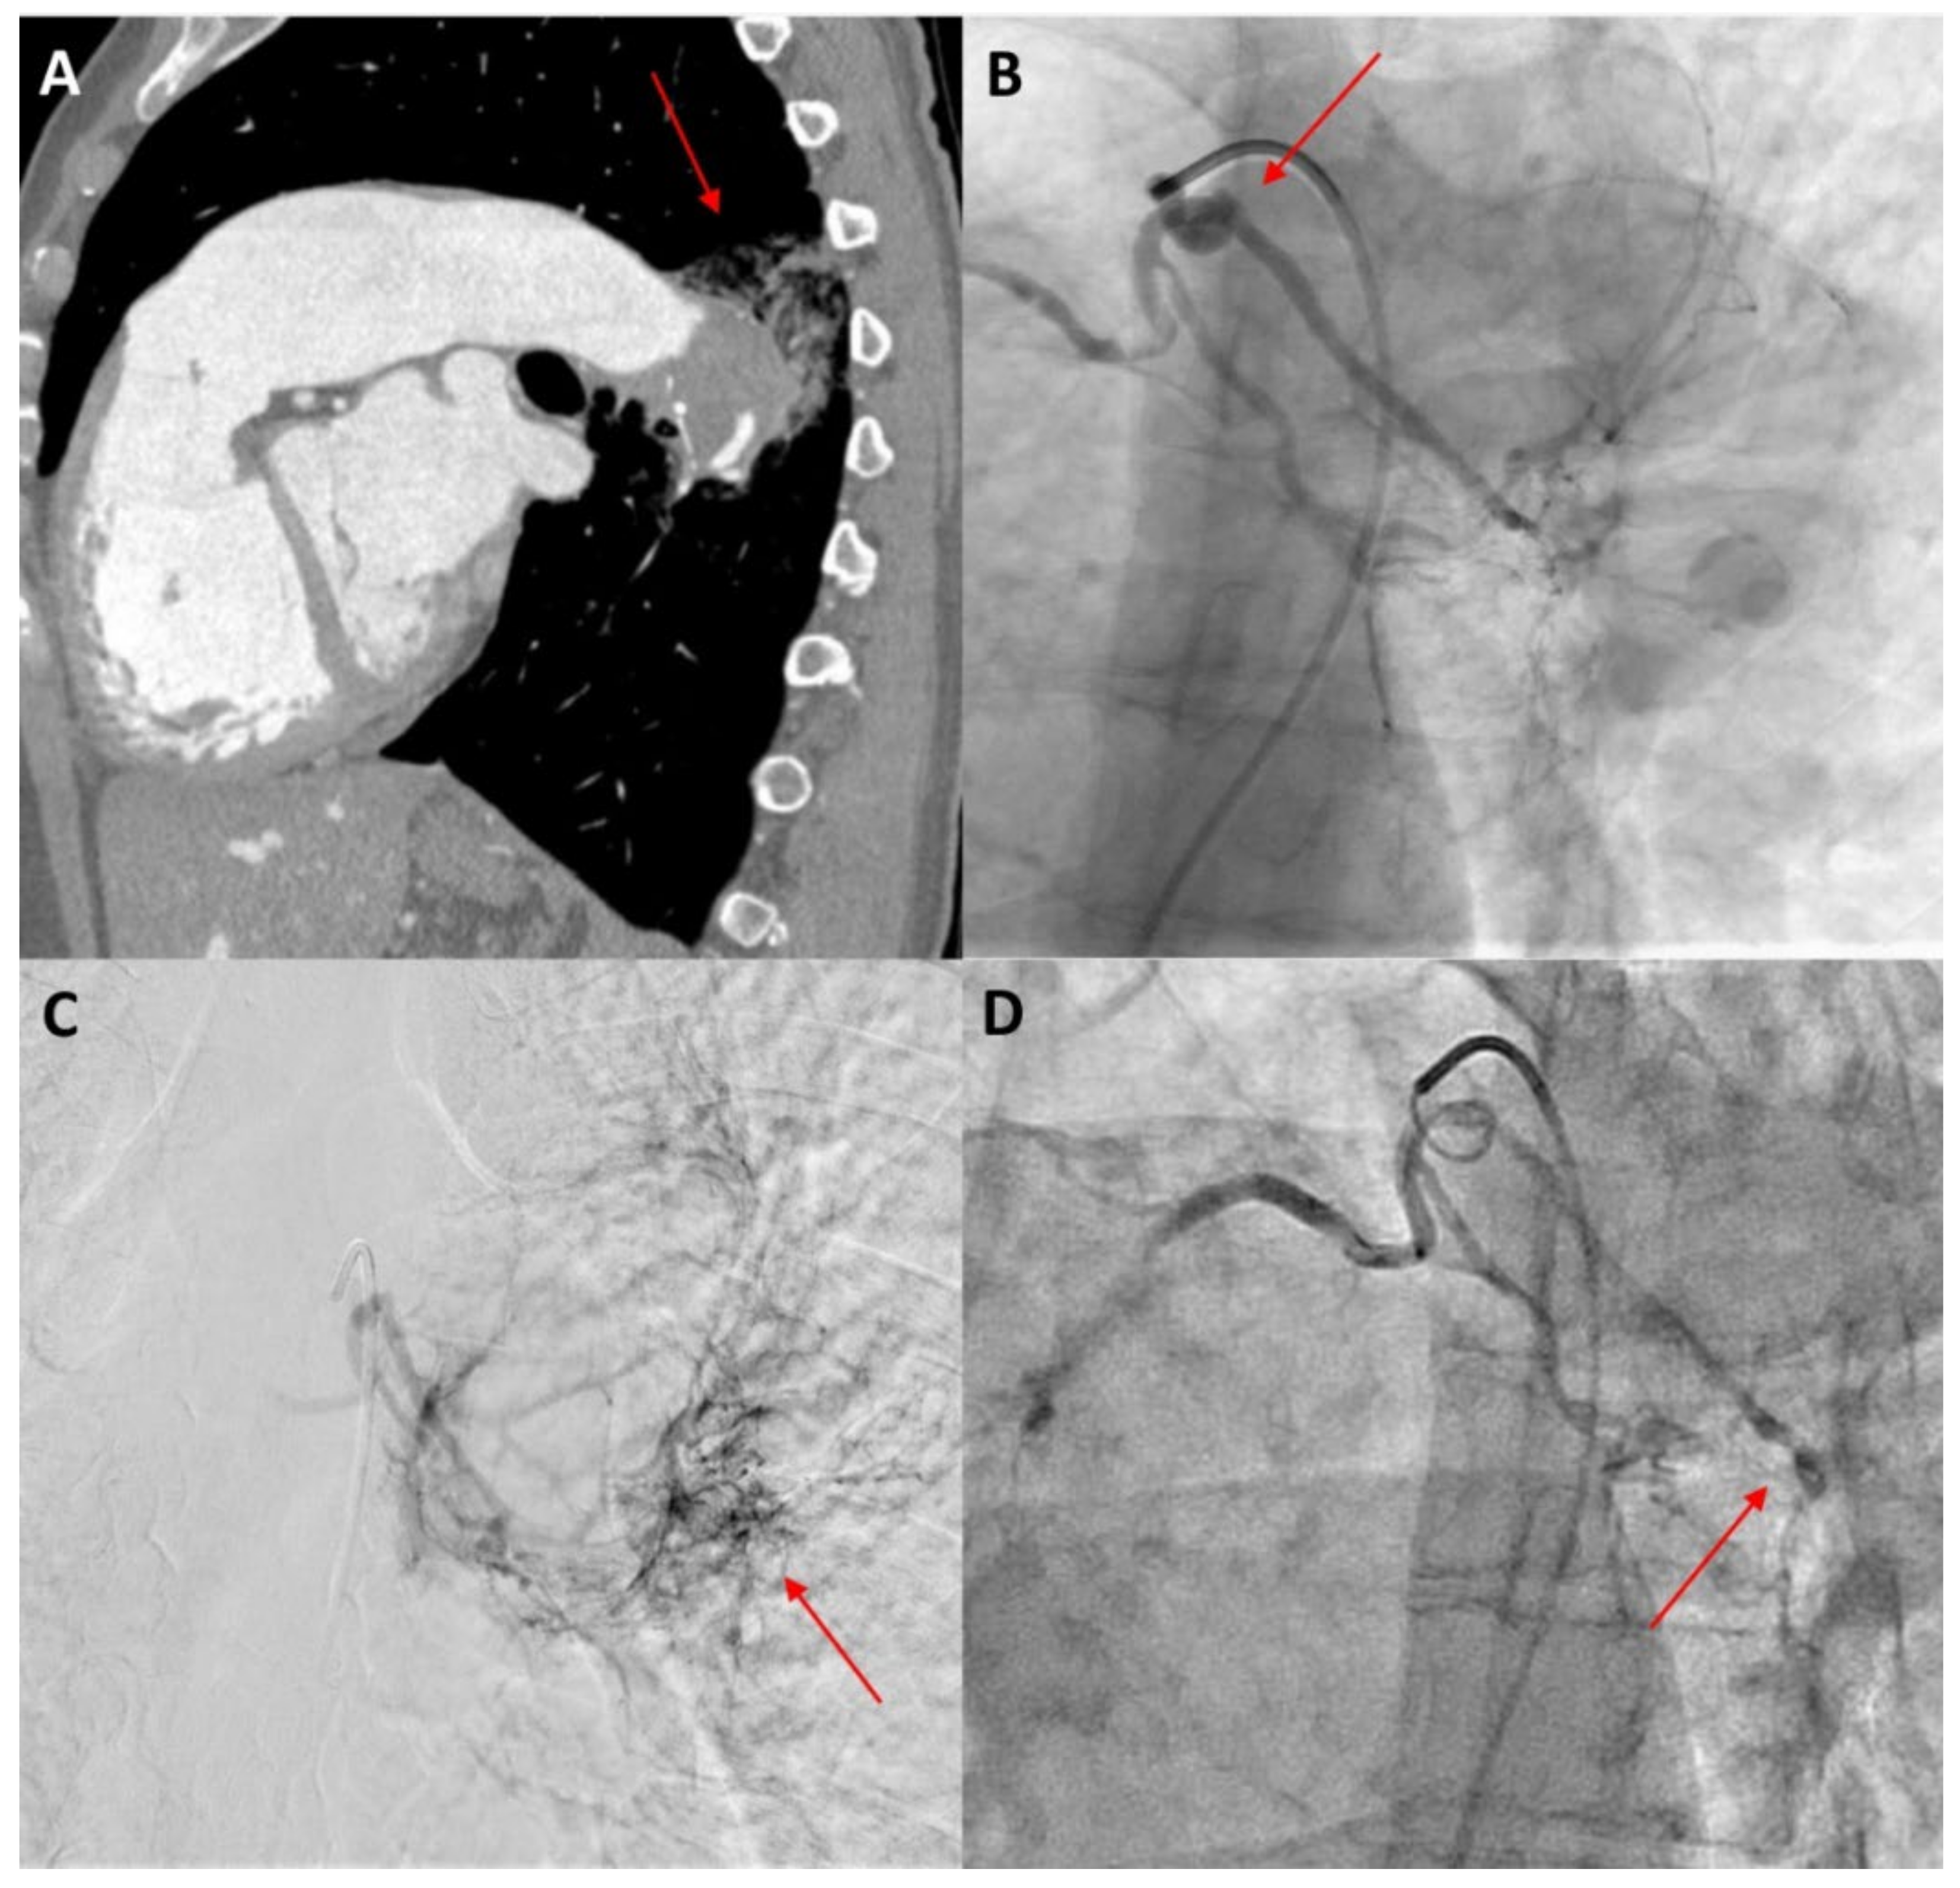

Bronchial artery embolization (BAE) is a minimally invasive and efficient technique in managing massive and recurrent haemoptysis as a single therapy or in combination with conservative medication or surgery [13,62]. BAE, first introduced by Remy et al. in 1974 [76], is performed in view of lowering the perfusion pressure by occluding the systemic arterial inflow of the culprit vessels [25]. As an overall success rate of 70–99% has been documented over the years, it is now considered as a first-line therapy to control haemoptysis in many cases [77]. Before the procedure, an arteriogram should be performed to visualize the responsible bronchial arteries and nonbronchial collateral arteries that will be the target of embolization [13,78] (Figure 3).

Figure 3.

A 40-year-old female patient with Eisenmenger syndrome on the background of a large secundum ASD presenting with recurrent episodes of haemoptysis. (A) Sagittal view of thorax computed tomography after intravenous contrast medium injection, showing aneurysmatic dilatation of the left pulmonary artery with intraluminal thrombus and adjacent post-bleeding infiltrations in the lung parenchyma (red arrow). (B) Catheterization of the bronchial arteries with a 5 Fr Cobra catheter, showing the tortuous origin of the left bronchial artery (red arrow). (C) Angiographic image in a delayed parenchymal phase, showing abnormal imaging of the left posterior lung parenchyma adjacent to the descending aorta, corresponding to the area of bleeding (red arrow). (D) Angiographic image after embolization with 100–300 μ particles through a 2.6 Fr microcatheter. The left bronchial artery could not be selectively catheterized, so injection of particles was performed in both bronchial arteries until stasis was achieved, especially in the left side (red arrow).

To date, corroborating evidence on the role of BAE in patients with PAH-CHD is limited and comes mostly from case reports and small cohorts. Successful and uncomplicated embolization of the bronchial arteries or the systemic-to-pulmonary collaterals has been described in several single cases of patients with ES [36,79]. Two observational studies that included 12 and 8 PAH-CHD patients presenting with haemoptysis (of which four patients had ES) confirmed the safety and efficacy of BAE in this specific population [78,80]. The estimated recurrence rate after BAE has been noted as being remarkably high in the latter cohort, rising to as much as 50% [80]. Generally, deficient embolization of the culprit vessels is responsible for early re-bleeding, whereas late-term recurrence may result from recanalization or further hypervascularization leading to the formation of new collaterals [13,81]. Combined therapy with BAE and TA may assist in achieving lower relapsing rates following BAE [62].